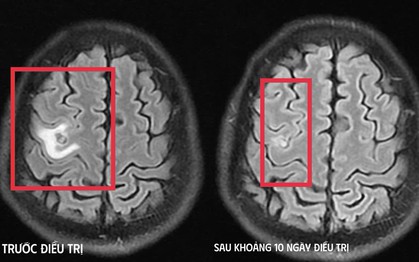

Người phụ nữ ở TP HCM bị "chết đuối trên cạn" được hàng xóm đưa đi cấp cứu kịp thời

(NLĐO) - Người bệnh sống một mình tại phòng trọ, đột nhiên đau ngực, khó thở, ngất xỉu, may mắn được hàng xóm đưa đi cấp cứu qua nguy kịch.